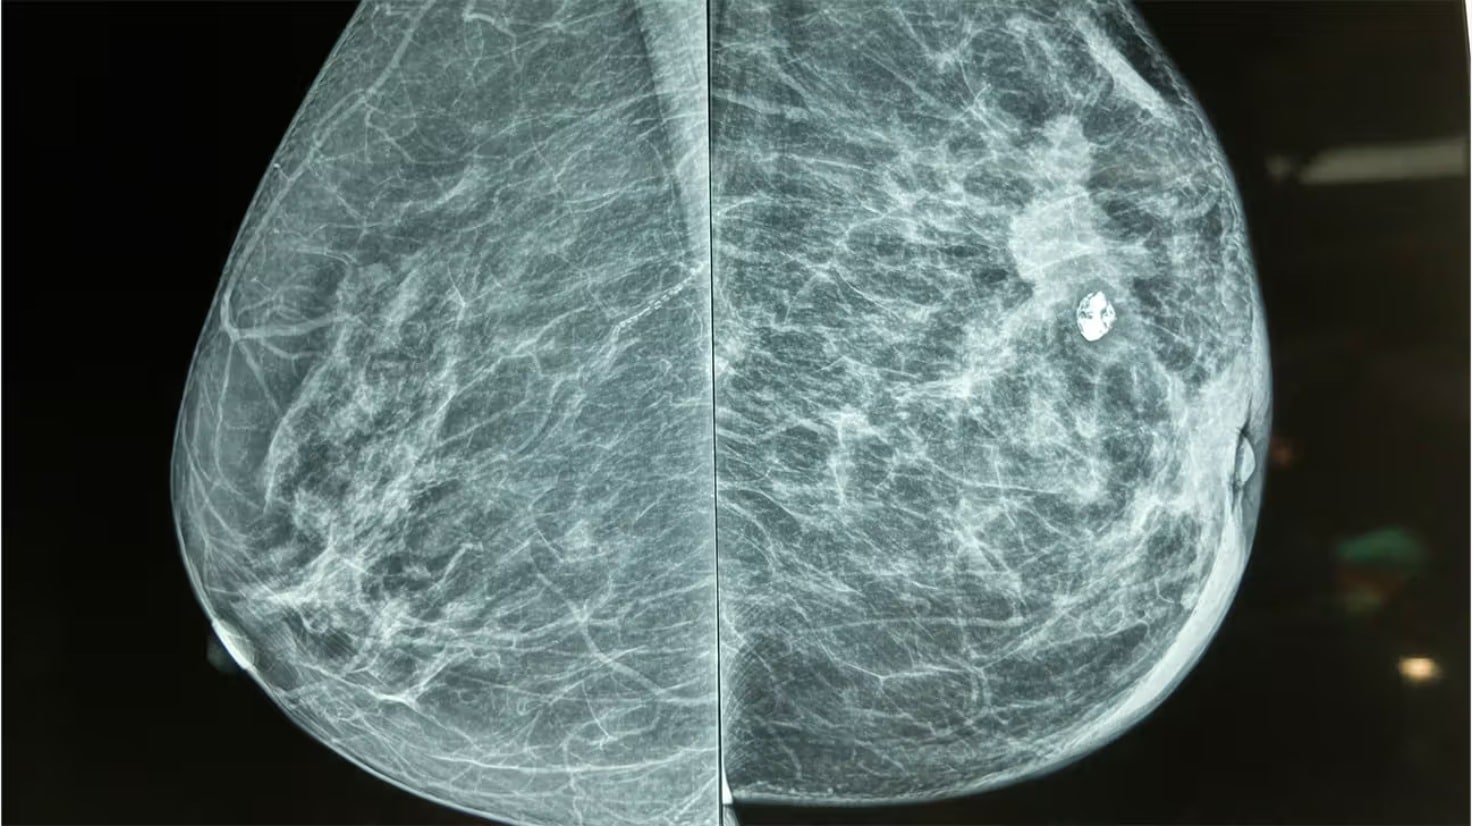

-هو عملية جراحية تهدف إلى إعادة بناء الثدي بعد استئصاله كلًيا أو جزئًيا،غالبًا ما بسبب سرطان الثدي، ويمكن أن يساعد ترميم الثدي في تحسين الحالة النفسية للمرأة وتعزيز ثقتها بنفسها، كما ُيمكن أن ُيساعد في استعادة التوازن الجسدي.